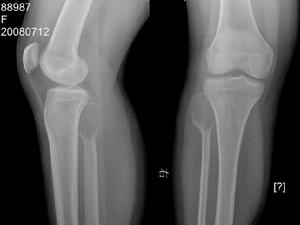

橈骨遠端骨腫瘤多數骨腫瘤的診斷較為複雜,有時存在一定的困難,因為不同骨腫瘤可有相近似的表現,良性骨腫瘤可發生惡變;有些骨腫瘤組織學檢查顯示分化良性,但臨床上表現為高度惡性,常常早期出現肺轉移。還有一些病變的臨床,X線或病理表現與骨腫瘤相似。一般來說,骨腫瘤的診斷必需強調臨床,X線表現及病理三結合,綜合分析,才能作出正確診斷。在診斷過程中,應注意區分幾個問題:①骨腫瘤與非骨腫瘤病性變;②良性骨腫瘤與惡性骨腫瘤;③原發性骨腫瘤與轉移性骨腫瘤。

骨腫瘤的診斷有的比較容易,單憑臨床檢查即可作出初步診斷,如表淺部,位的骨瘤或骨軟骨瘤等,有的在x線片上有特點,可根據典型的x線所見得出初步印象如

硬化性骨肉瘤、軟骨肉瘤等;有的則須結合臨床、x線和病理,綜合分析,才能作出正確診斷。因此,臨床、x線和病理被認為是診斷骨腫瘤的三個重要步驟,有時

是缺一不可的。尤其在考慮採用截除肢體的手術之前,一般都要經過上述三方面的檢查確診,才能決定。在鑑別診斷方面本病首先應與炎症鑑別。